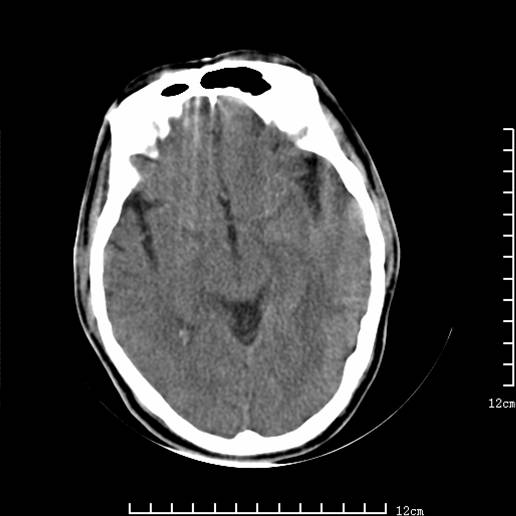

以下图像分别是3月25日凌晨及下午图像、3月27日、4月16日的ct图像。

3月27日

1)左侧额颞顶叶、岛叶及基底节区(相当于左侧大脑中动脉供血区)大面积脑梗塞。2)右侧基底节区腔隙性脑梗塞。

大脑中动脉供血区大面积脑梗塞没有问题。